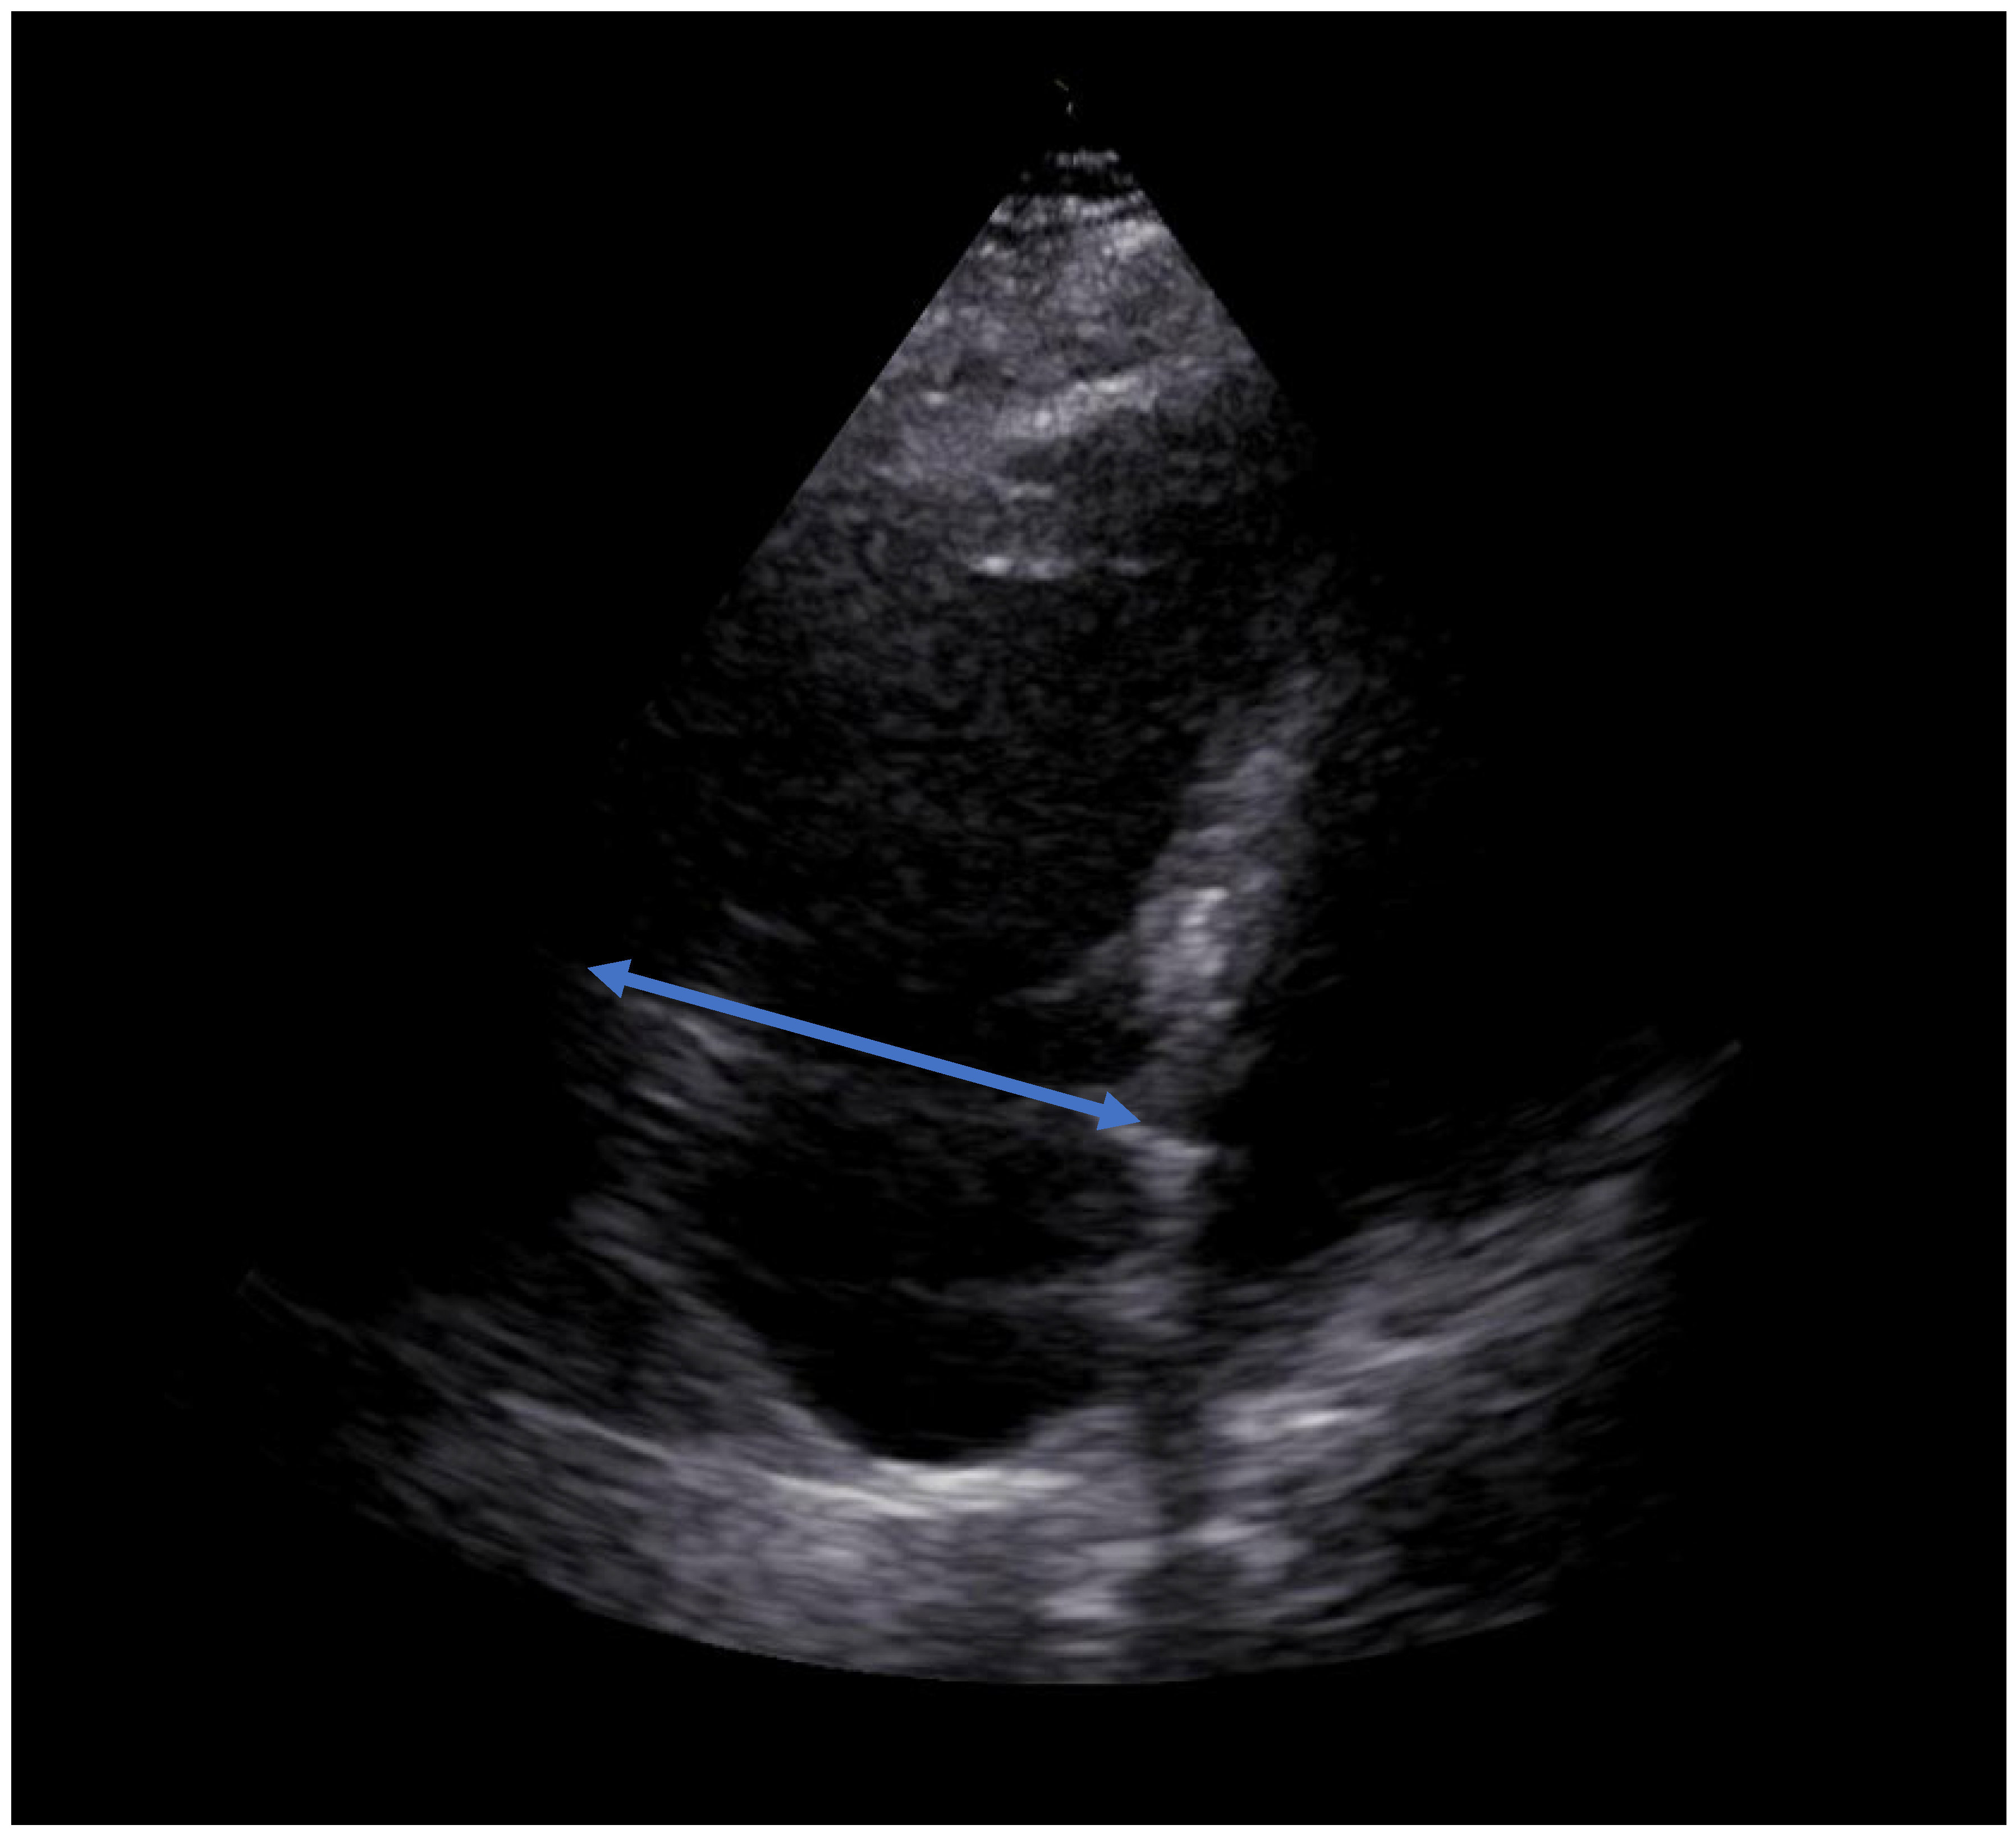

2. Case Report

| RVEDD [mm] | 65 | 49 | 37 |

| D- Sign | Yes | No | No |